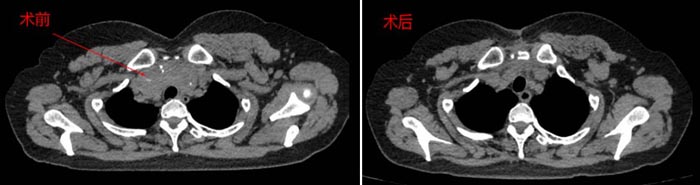

近日,患者刘女士因胸骨后巨大甲状腺肿来我院就诊,术前CT提示胸骨后有超过10公分的巨大甲状腺肿瘤,与胸主动脉、主支气管、无名静脉、心包等重要脏器都紧密粘连,手术稍有不慎,后果不堪设想。我院普外甲状腺病区医生团队接诊后,高度重视,邀请胸外科、麻醉科、重症医学科组成了MDT小组为其进行会诊,专家们为患者进行了详细的病情分析及风险评估,得到家属同意后,一致决定为其行“开放劈胸手术”。患者在各兄弟科室的通力协作下,历经5个小时,手术顺利,术后恢复良好。

患者术前术后影像学对比